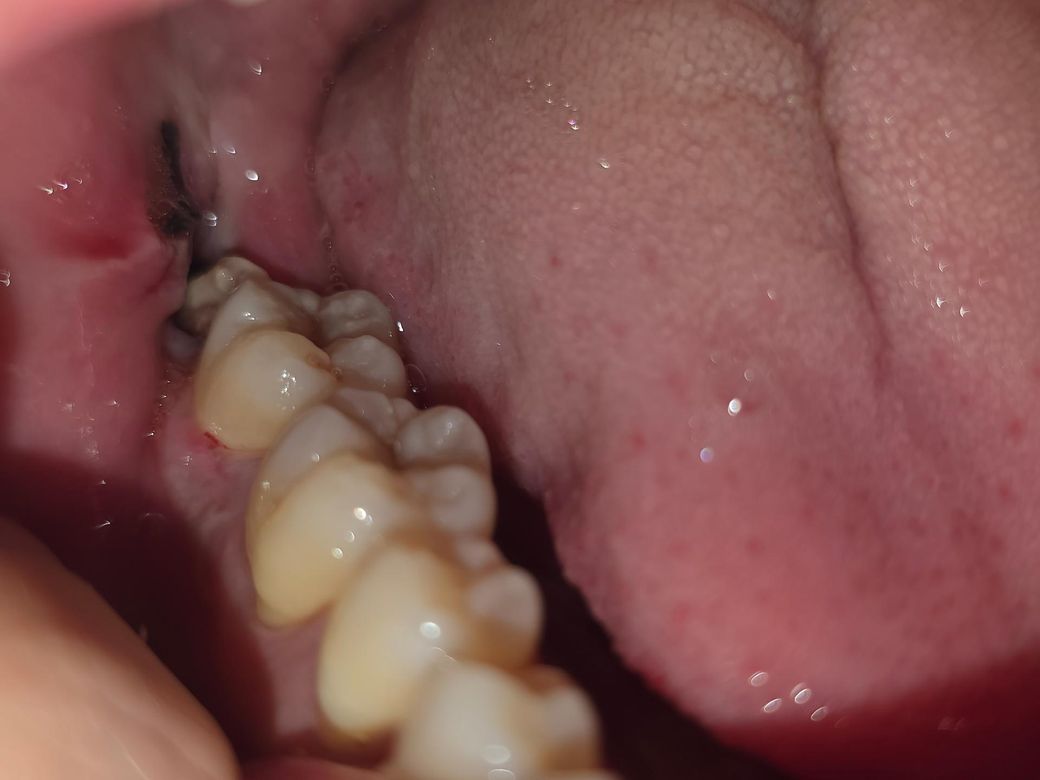

사랑니 발치한 지는 3일 됐습니다. 발치한 곳에 이상한 돌같은게 있는데 냄새가 진짜 너무 고약하고 이물감이 심해서 빼고싶은데 이게 뭘까요? 아프진 않습니다.. 냄새가 너무심해서 숨만쉬어도 나는거같아요

• 2번 째 사진

사랑니를 발치하고 나면 발치한 부위에 혈병이 형성되는 경우는 있습니다. 하지만 악취가 난다면 감염이 생겼을수 있습니다. 감염이 되었다면 감염의 원인을 제거하는것이 중요하기 때문에 자세한 확인을 위해서 치과에서 진료를 받아보는 것을 권유드립니다.